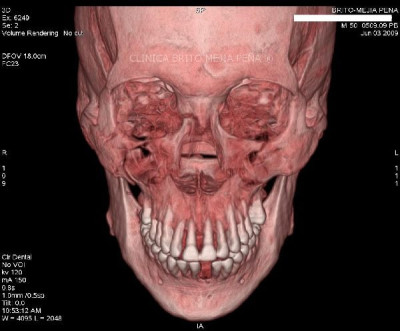

Detalle óseo